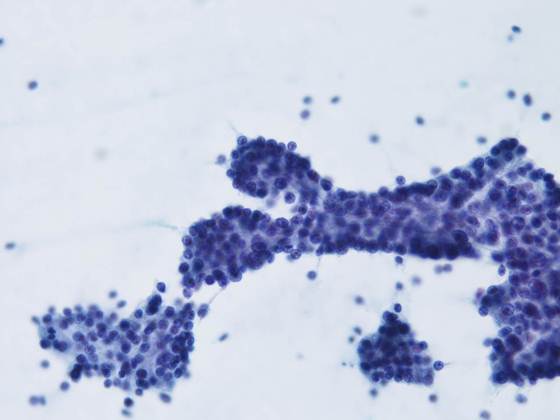

背景に組織球やライトグリーンに染まる顆粒が認められ、腺房を形成するような形態の細胞集塊が多数出現していた。

細胞質は境界不明瞭で、ライトグリーンに淡染する顆粒が認められた。

核は一部裸核状になり、小型類円形を呈し、クロマチンは細顆粒状で増量していた。